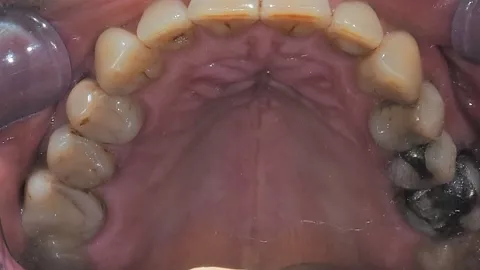

2a. 2b. Initial intraoral view of the molar.

2a

2b